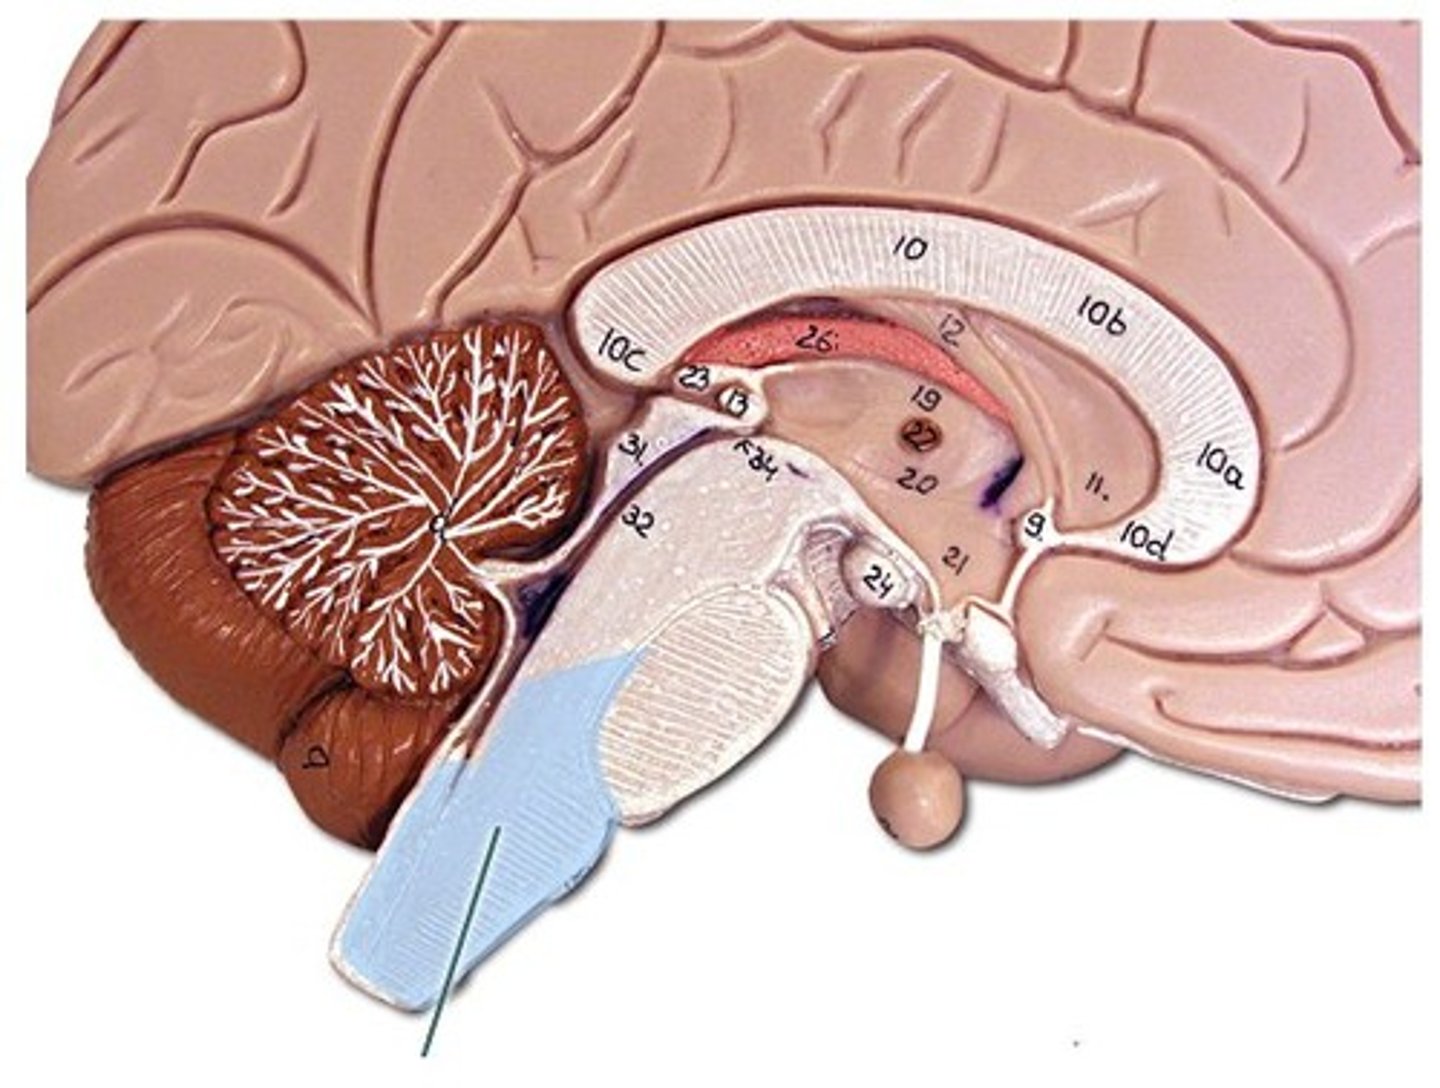

corpus collosum

part of the cerebrum. white matter. Myelinated Axons. It's job is to allow communication between the left and right hemispheres.

fornix

connects the hypothalamus and the hippocampus.

diencephalon

includes some of the area of the limbic system.

- acts as a connector in the brain.

- Connects cerebrum with the lower parts of the brain. Includes the pituitary gland, thalamus, hypothalamus, mammillary bodies, and pineal body.

pituitary gland

the thing it hangs from is the infundibulum (the stalk that it hangs from. It regulates hormones. Releases hormones that control other endocrine glands. Releases tropic hormones.

infundibulum

The stalk that the pituitary gland hangs from.

thalamus

receives and filters incoming sensory information. All the senses except for smell hit thalamus first. With generalized and specified senses.

interthalamic adhesion

in the center of the thalamus. It connects the thalamus in the right and left hemisphere of the brain.

hypothalamus

This is the big cross roads. Master control of the autonomic nervous sytem (heart rate, blood pressure, digestion, parts of urination, respiration).

- Master control of the endocrine system - secretes hormones that tell the pituitary gland what to do. Pituitary gland cannot act unless it has orders from hypothalamus.

- Makes some hormones too that it stores in pituitary gland.

- Regulation of body temperature.

- Control of emotional behavior (seat of the limbic system). Center of it.

- Helps us to integrate feelings/ have complex feelings.

- Controls food and water intake (initiates thirst mechanism) . detects blood osmolality.

- Regulation of sleep-wake (circadian rhythms).

mammillary bodies

two bumbs between pituitary gland and brain stem. Part of limbic system. Contributes to functioning of limbic system.

pineal body

considered an endocrine gland. Secretes melatonin. Plays a role in circadian rhythm - regulation of this. Sleep/wake cycles or night/day cycles. They don't know exactly how this works, but if the pineal gland does not release melatonin, you can have differences in circadian rhythm.

brain stem

Includes the mid brain, pons, and medulla oblongata.

midbrain

corpora quadrigemina,connector of cerebrum, diencephalon, and cerebellum to spinal cord. Connector in central nervous system.

corpora quadrigemina

Also known as the tectal plate. Consists of the superior colliculi and the inferior colliculi.

superior colliculi

bumby part on opposite side of pituitary gland. Top one. Responsible for visual reflex (track objects visually). If we see something in peripheray, we can turn towards object. Instinctive reflex.

inferior colliculi

bumpy part on opposite of pituitary gland. Bottom one. 31 auditory tracking. If we hear a loud noise, we can move toward it.

pons

contains parts of respiratory center. Plays a role in controlling breathing rate and depth.

medulla oblongata

has a cardiac center. Plays a role in influencing heart rate and the force of the contractions in the heart. In response to changes in blood pressure and oxygen levels.

- vasomotor center - helps to control blood pressure. Sends out signals that causes vasoconstriction or vasodilation of blood vessels. Contains parts of respiratory center.

- initiates inspiration and respiration.

cerebellum

cerebellar hemispheres, cerebellar cortex, and arbor vitae.-

the little brain.

- Function: coordinates all voluntary movements. Ability to ride a bike, dance, anything complicated that calls for coordinating movement between left and right sides with skeletal muscles.

- Ability to move joints in a coordinated fashion- cerebellum in charge.

cerebellar hemispheres

divided by vermis.

cerebellar cortex

outer covering of cerebellum - gray matter.

arbor vitae

"tree of life" white matter in cerebellum.

ventricles

cavities in the brain. Includes lateral ventricles - right and left, third ventricle, fourth ventricle, cerebral aqueduct, and choroid plexus.

third ventricle

in the area where the hypothalamus is.

fourth ventricle

located beneath the arbor vitae in the cerebellum.

cerebral aqueduct

connector between third and fourth ventricle in front of colliculi.